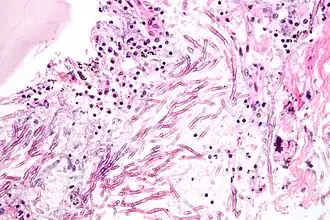

Micozele sunt boli infecțioase ale omului, animalelor și plantelor produse de microorganisme din regnul Fungi (ciuperci microscopice).

Ciuperca microscopică patogenă care poate fi și sub formă de spori pătrunde printr-o așa numită „poartă de intrare” în organism, care poate fi pe cale aerogenă, digestivă sau prin piele. Aici începe să se înmulțească producând simptomele bolii care în general nu sunt specifice unei infecții micotice.